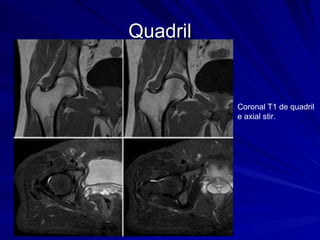

Quadril Coronal T1 de quadril e axial stir.

Quadril Coronal T1de quadril e axial stir.